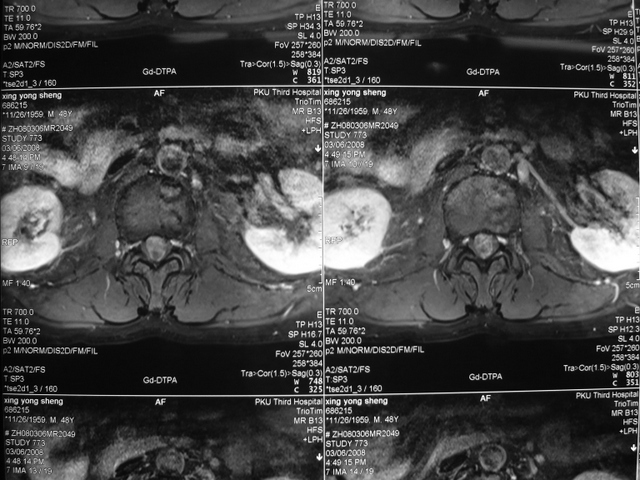

圆锥畸胎瘤